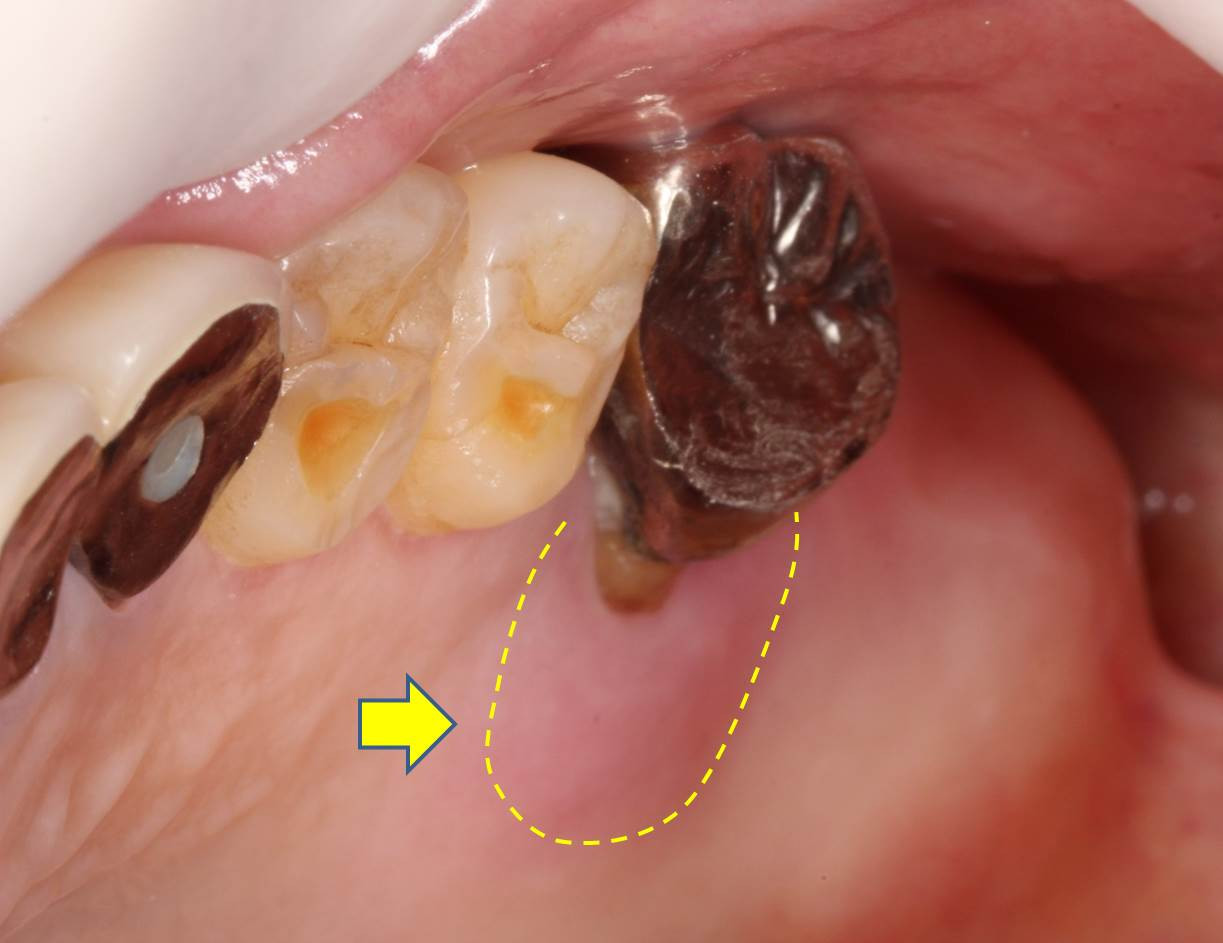

歯周病治療の相談で受診される患者様が増えています。他のかかりつけの歯科医院がある患者様で、3カ月ごとの定期検診に欠かさず受診していらしたようですが、歯茎が腫れたので近くの歯医者さんに診てもらうと「抜歯」を宣告されたとのことでした。定期検診に通われていたのに、非常に残念なケースだと思います。銀歯の根本の歯茎(黄矢印部)が腫れて盛り上がり、少し赤みを帯びているのが分かります。圧迫で膿が出てくる状態でした。

誠に残念ながら、パノラマレントゲン、デンタル、CT撮影を実施し、残せる手立てはないか精査致しましたが、当院の診断も重度歯周病で治療法は「抜歯術」の適応となり、施術致しました。

抜歯した歯を見ると、第一大臼歯は3根に分かれており、歯根分岐部から口蓋根にかけて縁下歯石が付着していることが確認できます。「歯石」とは歯周病細菌が固着しバイオフォルムを形成している状態で、歯根に付着して歯槽骨破壊や歯肉の炎症惹起などの悪影響を及ぼします。無症状性に進行することも多く、「サイレントキラー」と呼ばれる所以でもあります。